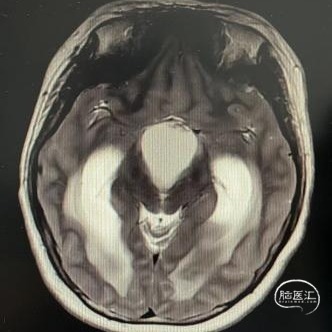

头部MRI显示:鞍区-鞍上区-第三脑室可见一不规则囊状长T1极长T2信号灶,大小约43mm*32mm*43mm,增强后可见病灶不均匀明显强化。垂体及视交叉未见显示,双侧脑室扩张,双侧脑室旁可见对称性斑片状长T1长T2信号灶。